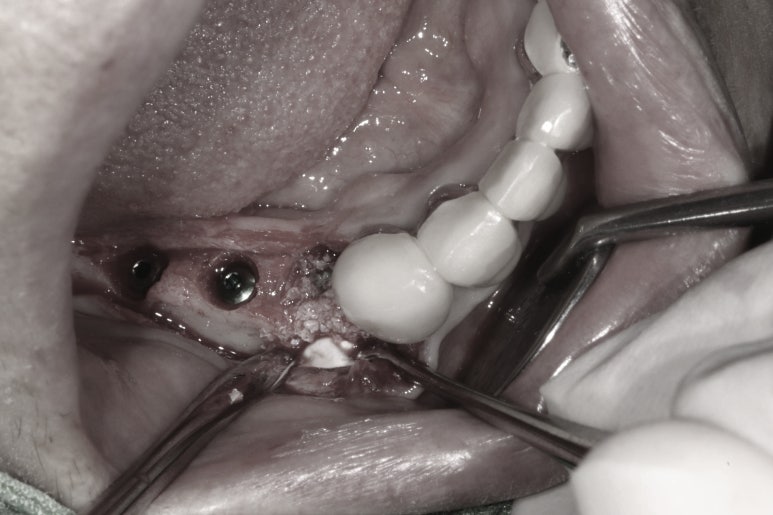

저희 치과는 덴티움 社의 골이식재 osteon III와 차폐막 collagen membrane을 씁니다.

아무리 CT를 통해 미리 모든 계획을 한다고 해도, 수술에는 늘 변수가 있기 마련이며 위에 보시다시피 임플란트 주변 치조골 이식술을 함께 해야하는 경우 약간의 임플란트 위치 수정도 필요하기 때문이죠.

게다가 수술 전 CT를 사용한 수술 계획은 근본적으로 완벽할 수 없는 근거가 있습니다.

바로 '잇몸'을 고려할 수 없는 치료계획을 세우게 된다는 것인데요.. CT 상에서 잇몸은 보이지 않기 때문에 어찌보면 당연한 것.. 주변 잇몸부터 잇몸뼈, 치조골이식술, 임플란트 위치오 보철물의 형태까지 - 종합적으로 생각해가며 수술을 해야하기에 반드시 경험있는 치과의사에게 치료받기를 권해드리는 것입니다.

수술이 끝나고 깔끔하고 예쁘게 꿰매드렸습니다.

임플란트 개수 자체는 많지만, 네비게이션 임플란트 수술 시스템을 이용하여 빠르고 덜 침습적인 수술을 하게 됨으로써 수술 후 통증을 최소화 시킬 수 있습니다.